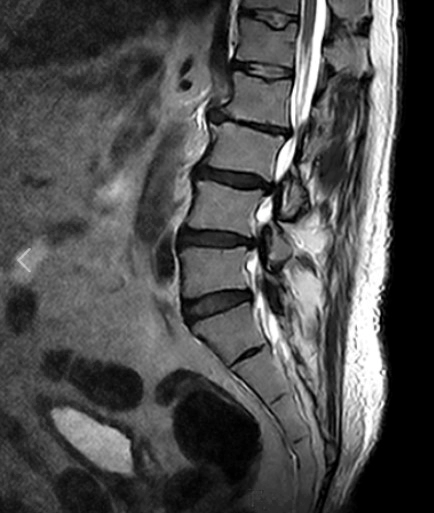

요추 염좌 통증 원인 증상 4가지 및 요추부 염좌 회복기간 및 스트레칭

요추 염좌는 요추부의 근육이나 인대에 손상이나 과도한 늘어남이 발생하는 상황을 말합니다. 이는 많은 사람들이 경험하는 흔한 허리 부상 중 하나로, 일상 활동에 지장을 줄 수 있는 통증과 불편을 초래합니다. 이에 요추 염좌의 통증 원인과 주요 증상 4가지를 알아보고 회복 기간과 증상 완화에 효과적인 스트레칭에 대해 자세히 알아보겠습니다.

요추부 염좌 회복기간

요추부 염좌 회복 기간은 부상의 정도에 따라 달라질 수 있지만 미세한 염좌의 경우, 적절한 휴식과 치료를 통해 2~4주 정도 소요될 수 있습니다. 그러나, 중등도에서 중증의 부상의 경우 몇 달이 걸릴 수 있으며, 완전히 회복되기까지 6개월 이상 걸릴 수도 있습니다.